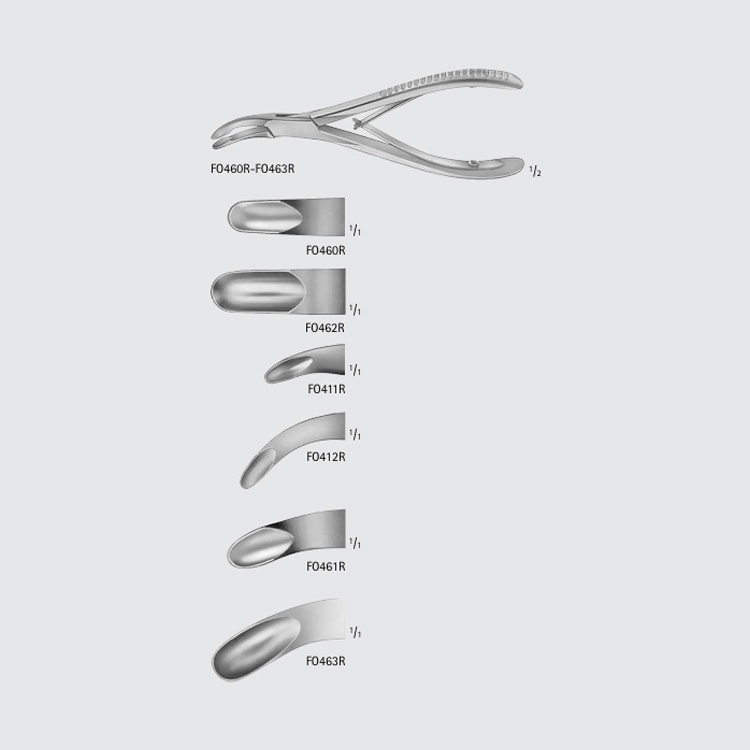

LUER Bone Rongeur

CatalogNumber Jaw Size(mm) Jaw Length(in.)

FO460R 7.5 x 25 STR 6 7/8

FO462R 9.5 x 33 STR 7

FO411R 4.2 x 20 CVD 6

FO412R 4.2 x 26 STRONG CVD 6 1/8

FO461R 7.5 x 24.5 CVD 6 7/8

FO463R 9.0 x 30 CVD 7